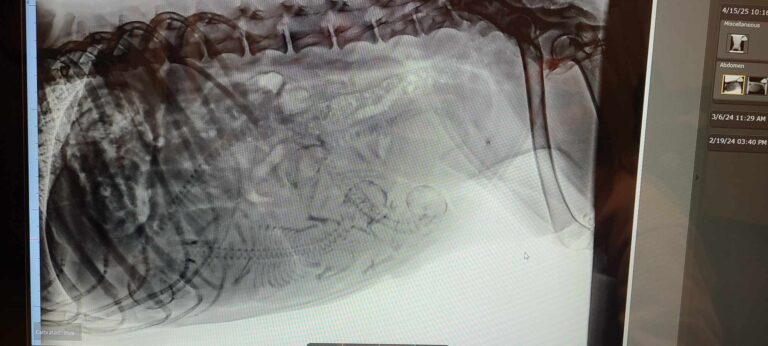

Radiographie du 15 avril

radiographie de de Oak gestante